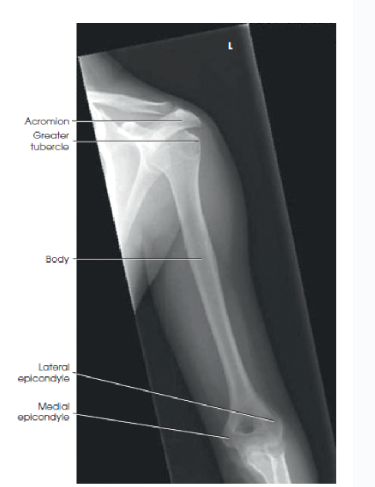

Eval: what should be in profile for a lateral humerus?

A

the lesser tubercle on medial aspect

eval: what structures should be superimposed in a lateral humerus?

the humeral epicondyles

greater tubercle superimposed over the humeral head